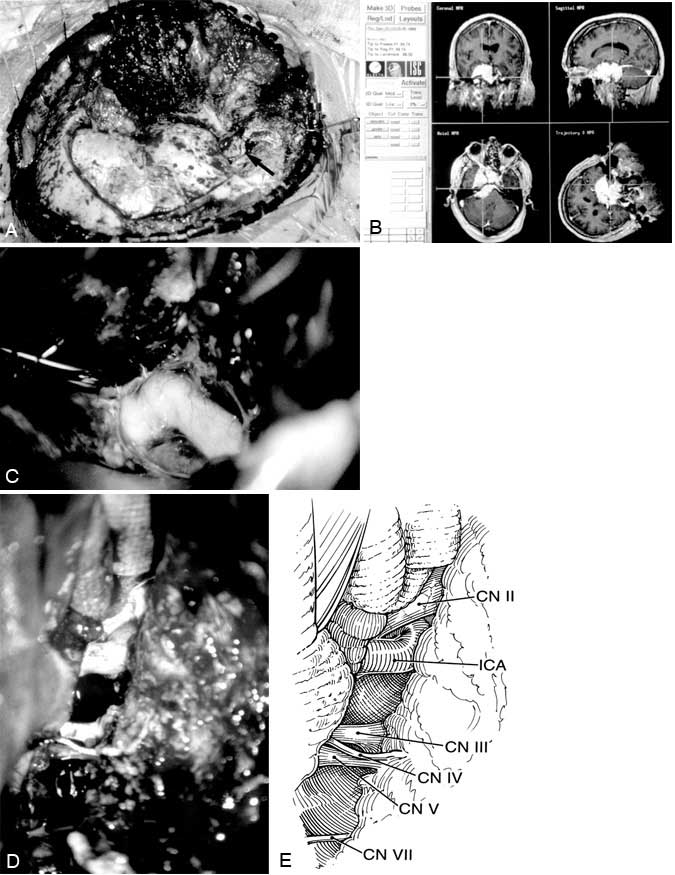

An orbitozygomatic-combined supra- and infratentorial approach with transcochlear petrosectomy was performed. Tumor encased the optic nerves, optic chiasm, pituitary stalk, internal carotid arteries, and the oculomotor, trochlear, trigeminal and abducent nerves and displaced the basilar artery and the facial and vestibulocochlear nerves. These neurovascular structures were dissected from the tumor, and all cranial nerves were left intact (Fig. 2). Resection of tumor in the cavernous sinus and sella was not attempted. Postoperative images demonstrated substantial tumor resection (Fig. 3). Meningioma was diagnosed by pathologic examination.

The dura is incised in the shape of a “3,” with the anterior incision centered about the pterion and the posterior incision centered about the petrous bone. The incision simply joins a standard pterional dural flap with the dural incision of the combined approach. The latter begins over the temporal lobe, crosses the superior petrosal sinus below its entrance into the sigmoid sinus, and curves inferiorly in front of the sigmoid sinus to the jugular bulb. The superior petrosal sinus is coagulated and divided, and the tentorium is cut medially to the tentorial incisura and posteriorly to the trochlear nerve. This maneuver connects the supra- and infratentorial compartments and relaxes the neural structures. The petroclival region, brain stem, cranial nerves, and blood vessels of the posterior circulation are exposed (Fig. 2) and the pathology can be accessed.